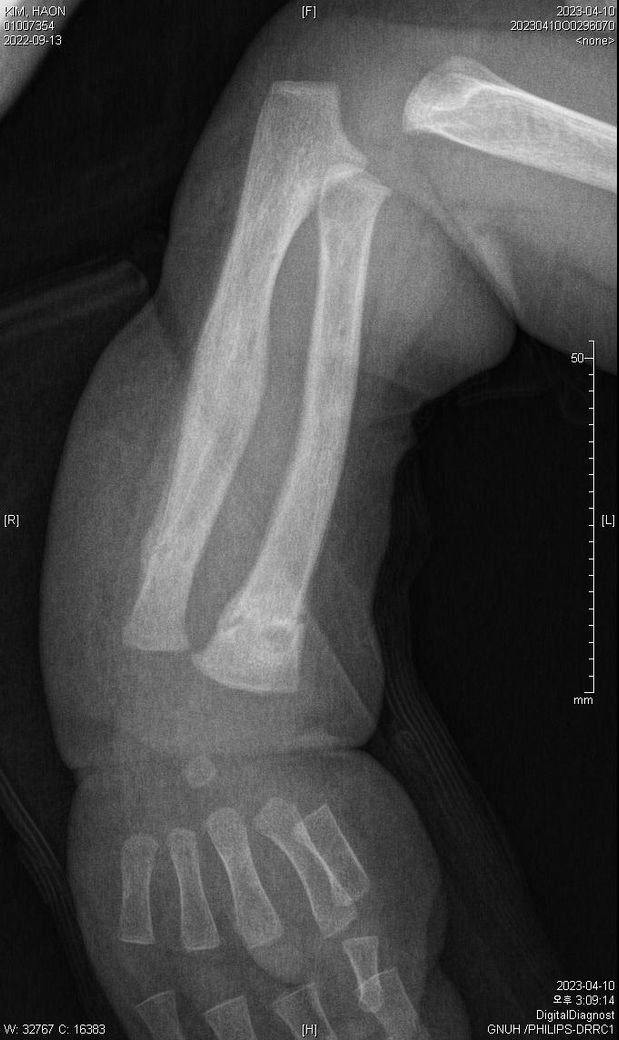

다름이 아니라, 첨부드린 엑스레이(X-ray) 사진처럼 골절 사실을 알게 되고 골절 발생 시점 대략적으로나마 추정시기를 파악하려고 문의 드리게 되었습니다

첨부드린 파일에도 있지만 4월 10일 사진에서는 유합 직전의 상당량의 켈로스 라는 것이 발견된다고 합니다.

• 4번 째 사진

다만 "3월 30일 영상에서 골절선이 비교적 뚜렷하고, 4월 10일에 상당한 가골(callus)이 형성"된 점을 종합하면 "골절은 3/30 당일보다는 최소 수일~2주 이상 이전에 발생했을 가능성이 높습니다."

영아(12개월)는 성인보다 "가골 형성이 빠르기 때문에, 4/10의 소견은 대략 골절 후 10~21일 전후 범위"로 해석하는 것이 의학적으로 가장 보수적 입니다.

즉, 의학적 추정 범위로는 "3월 중순 전후(약 1~3주 전 발생)"가 합리적 이며, 그 이상 정밀한 특정은 영상만으로는 어렵습니다.

올려주신 사진을 참고하였을 때 3월말에는 켈로스(가골)형성이, 4월에는 유합이 진행되고 있는 상태를 고려해볼 수 있겠습니다.

회복 경과를 바탕으로 대략적인 시점을 고려하여 보자면 3월 말 시점에서 약15-20일 정도의 기간을 골절 발생시기로 의심해볼 수 있겠지만, 정확한 소견은 관련 전문의의 의견을 들어보심이 좋습니다.